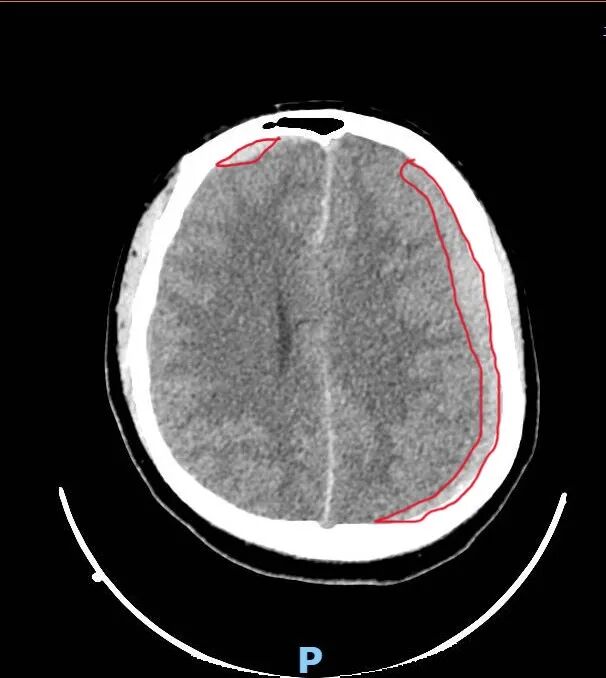

头颅CT显示:颅内大出血,血肿正在压迫大脑中枢。

入院第三天,小程开始出现烦躁、胡言乱语。复查CT显示:血肿扩大,脑组织受压,出现“大脑镰下疝”——这意味着,控制呼吸和心跳的脑干随时可能被压迫,导致呼吸心跳骤停。

半个多月里,医护人员日夜守护,奇迹悄然发生:凝血功能逐步稳定;头颅CT显示:出血停止,血肿开始吸收;意识恢复,生命体征平稳,小程顺利转回普通病房。